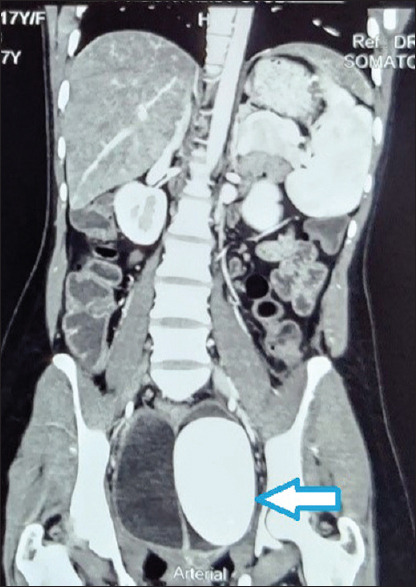

摘要:原发性阴道结石在儿童中并不常见。女性尿道重复与复杂的先天性畸形有关。我们报告了一例 46 岁女性肛周持续性尿道窦,伴有阴蒂肥大和阴茎尿道、阴囊样囊袋、双子宫和半阴道梗阻,以及巨大阴道结石。一名 16 岁女孩因腹部疼痛和直肠周期性排出血块而就诊。她的左侧髂骨区有一个触痛的肿块,像阴茎一样突出,下面有一个瘤状囊。阴道口缺失。计算机断层扫描显示她有两个子宫角和一个独立的宫颈,半侧阴道胀大且不相通,左侧半侧阴道内有一个巨大的钙化椭圆形肿块。探查时,从左侧半阴道取出了结石。左侧半阴道内发现的巨大结石似乎是所有症状的起因。它阻塞了左侧半阴道,使左侧子宫角充满经血,导致其逐渐增大并继发感染。只有在住院分娩时才能确保对这种异常情况进行早期诊断和及时转诊。对于发展中国家的大部分新生儿来说,能够负担得起或甚至被转诊到处理此类病例的机构都是一件奢侈的事情。我们希望通过本报告弥合医疗保健系统在知识、态度和实践方面存在的差距。

Abstract: Primary vaginal calculi are uncommon in children. Urethral duplication in females is seen to occur in association with complex congenital malformations. We report the case of perianal persistent urogenital sinus with a hypertrophied clitoris with phallic urethra, scrotum-like pouch, uterus didelphys with obstructed hemivagina, and giant colpolithiasis in 46XX female. A 16-year-old presented with pain abdomen and cyclic passage of blood clots per rectum. She had a tender lump in left iliac region, a phallus like protrusion and a ruggous sac below it. Vaginal opening was absent. Computed tomography showed two uterine horns with a separate cervix and distended non-communicating hemivaginas with a large calcified oval mass in the left hemivagina. On exploration, calculus was extracted from the left hemivagina. The large calculus found in the left hemivagina appears to be the cause of all presenting symptoms. It obstructed the left hemivagina, filling the left uterine horn with menstrual blood causing its gradual enlargement and secondary infection. The early diagnosis and prompt referral of such an anomaly can only be ensured in institutional deliveries. For a significant proportion of newborns in the developing world, the ability to afford or even be referred to institutes which deal with such cases is a luxurious affair. We hope to bridge bridging the knowledge, attitude and practice gap that exists in our health-care system with this report.